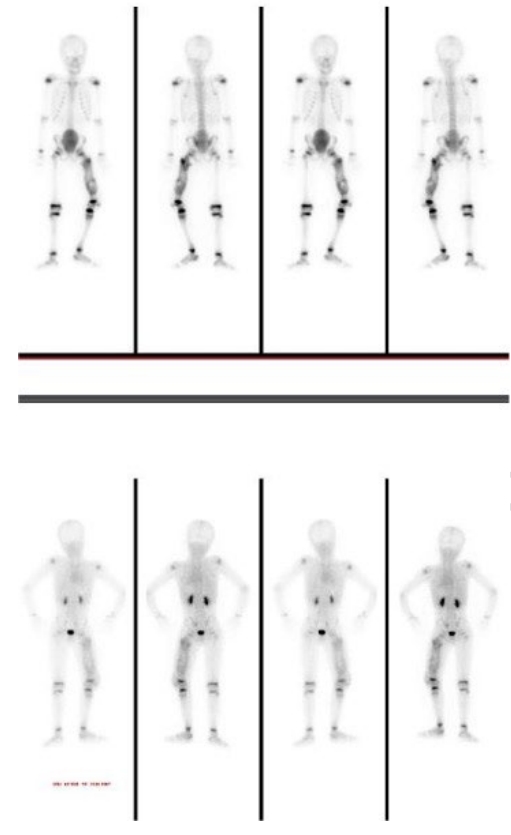

Fig. 1). Computed tomography confirmed chronic osteomyelitis (

Fig. 2) and demonstrated extensive HO. Subsequent management included joint aspirations and scheduled procedures, such as nail removal and bone biopsy.

Fig. 2.Noncontrast computed tomography of the left thigh with multiplanar re-formations showing post-nailing fixators in the left femur. Written informed consent for the publication of this image was obtained from the patient.